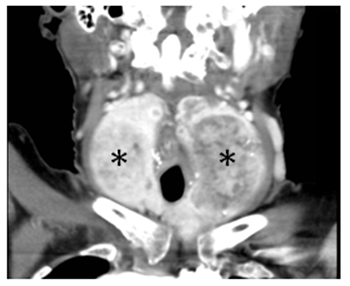

Laboratory testing reveals a TSH 1.14μU/mL (0,35-5,28). Chest radiography does not show tracheal deviation. Gastroscopy does not present esophageal alterations. Cervicothoracic CT shows a multinodular goiter with posteromedial spreading of both lobes that compress faryngoesophageal union and proximal esophagus (black arrows in Figures 1 and Figure 2). Also, larynx and trachea are displaced forward (white arrows in Figures 1 and Figure 3). Right thyroid lobe measures 5,2x4,9x7,8cm. Left thyroid lobe measures 5,7x4,9x8,8cm. Patient is dismissed for surgery due to high anesthetic risk. Currently, patient tolerates turmix diet and fluids with thickeners. Although isolated dysphagia is an uncommon symptom in compressive goiters, whose main manifestation is dyspnea, it is important to rule out an enlargement of the thyroid gland as a cause of dysphagia even in the absence of dyspnea, dysphonia or visible goiter.

Figure 2